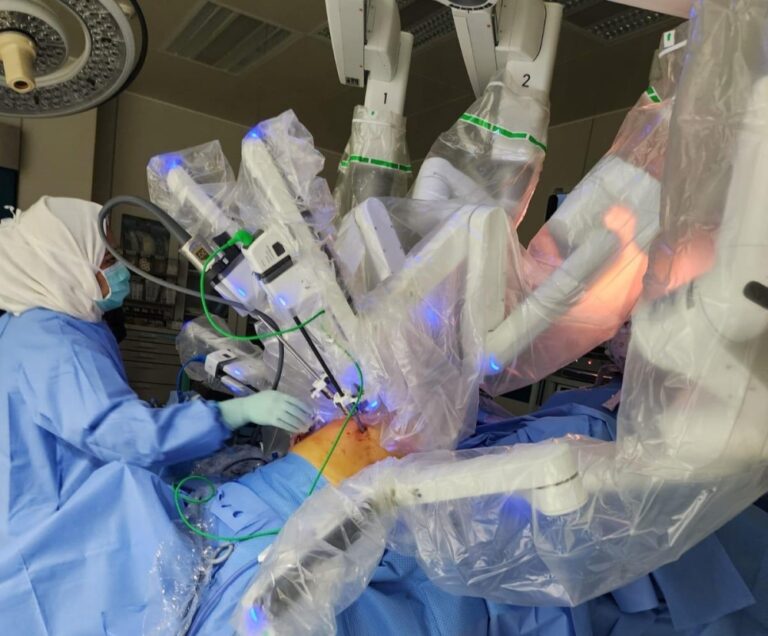

السعودية“طبية مكة”.. استئصال رحم وعقد لمفاوية لستينية باستخدام الروبوت الجراحيمايو 27, 2025